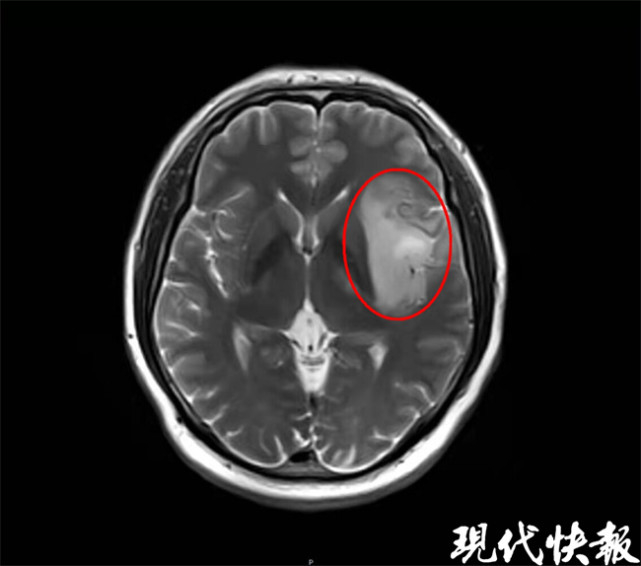

△傅涛的脑部核磁共振影像

2021年底,48岁的傅涛(化名)突然头痛、发热、流涕,一开始觉得是感冒,对症治疗了一段时间却没有明显改善,头痛症状愈演愈烈。约摸半个月后,傅涛发现自己味觉明显减退、一侧肢体麻木伴乏力,看东西有重影,赶紧到就近医院做了头部核磁共振检查,诊断为脑胶质瘤。随后,傅涛又赶往上海某医院就诊,医生查看影像报告后,也认为胶质瘤可能性大。(脑胶质瘤是因为大脑和脊髓胶质细胞癌变所产生的最常见的原发性颅脑恶性肿瘤。具有发病率高、复发率高、死亡率高以及治愈率低的特点)

接连两家医院给出了胶质瘤的诊断,对傅涛的打击巨大。抱着最后一丝希望,他又来到江滨医院,神经内科主任于明让其做了一次核磁共振,很快就发现了疑点。

“两次检查相差仅20天,但脑部病灶却出现了明显变化,而胶质瘤短时间内发生变化的可能性不大,所以我认为可以排除。”于主任随即围绕傅涛流行病史进行了深度挖掘,发现其是个旅游达人,发病前曾前往西藏、四川等多地旅游,并多次因食用未煮熟的牛羊肉发生腹泻。傅涛同时提到,自己向来喜食生食,很多肉等不及煮熟就下了肚,这让于主任立刻联想到了脑寄生虫病的可能。

通过一系列检查,很快揪出了元凶——弓形虫。于主任介绍,患者多是因为食用了有弓形虫的生肉,虫卵或虫子进入消化道后,一步步爬到了脑子里。